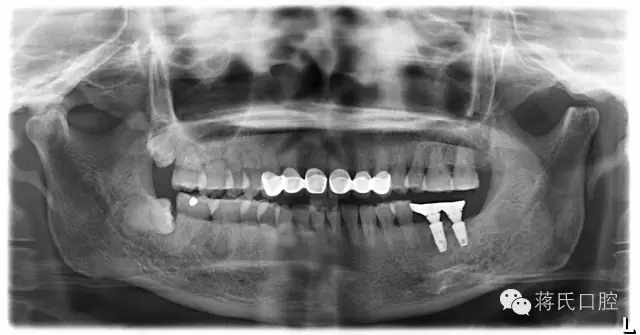

4.修復(fù)后正面,咬合距離低以純鈦冠修復(fù),植體角度良好所以連冠修復(fù)

6.修復(fù)后全景片